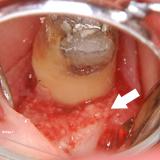

| 歯槽膿漏によって失われた骨が再生しています。 | ![]() |

![]() |

【術前】 |

【術後】 |